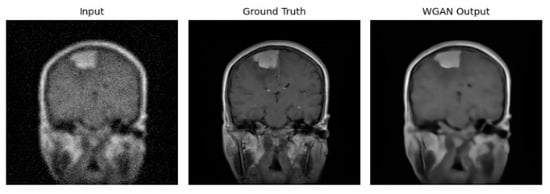

The rapid development of Generative Adversarial Networks (GANs) has transformed medical image processing, enabling realistic image synthesis, augmentation, and restoration. This study presents a comparative evaluation of three representative GAN architectures, Pix2Pix, SPADE GAN, and Wasserstein GAN (WGAN), across multiple medical imaging tasks,

The rapid development of Generative Adversarial Networks (GANs) has transformed medical image processing, enabling realistic image synthesis, augmentation, and restoration. This study presents a comparative evaluation of three representative GAN architectures, Pix2Pix, SPADE GAN, and Wasserstein GAN (WGAN), across multiple medical imaging tasks, including segmentation, image synthesis, and enhancement. Experiments were conducted on three benchmark datasets: ACDC (cardiac MRI), Brain Tumor MRI, and CHAOS (abdominal MRI). Model performance was assessed using Fréchet Inception Distance (FID), Peak Signal-to-Noise Ratio (PSNR), Structural Similarity Index (SSIM), Dice coefficient, and segmentation accuracy. Results show that SPADE-inpainting achieved the best image fidelity (PSNR ≈ 36 dB, SSIM > 0.97, Dice ≈ 0.94, FID < 0.01), while Pix2Pix delivered the highest segmentation accuracy (Dice ≈ 0.90 on ACDC). WGAN provided stable enhancement and strong visual sharpness on smaller datasets such as Brain Tumor MRI. The findings confirm that no single GAN architecture universally excels across all tasks; performance depends on data complexity and task objectives. Overall, GANs demonstrate strong potential for medical image augmentation and synthesis, though their clinical utility remains dependent on anatomical fidelity and dataset diversity.